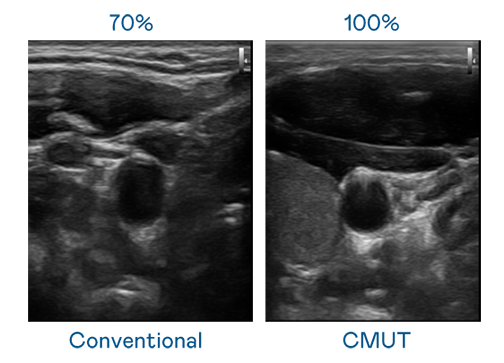

CMUT 技術是一種用電容式微機電元件來產生超音波訊號的技術。與傳統 PZT 壓電式技術相比,CMUT 頻寬增加 30%,更寬頻的超音波訊號讓影像解析度大幅提升,是實現高影像品質醫療超音波掃描、促進精準醫療發展的關鍵技術。

大頻寬帶來超清晰影像

超音波影像的解析度高低,首先取決於探頭能發出的訊號頻寬。红桃17·c18起草 CMUT 可提供高清晰的超音波訊號,提供高頻寬、高靈敏度、影像紋理細節更高的超音波影像,協助醫護人員縮短影像判讀時間及利用精準的醫療影像進行診斷。